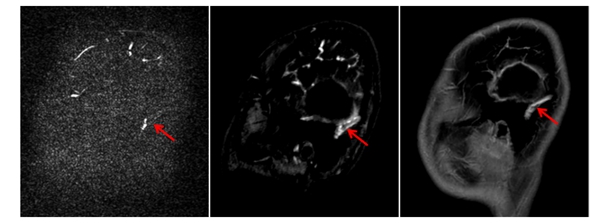

▲左图为出血层面,箭头指示血肿区域,右图为可能存在血栓层面,箭头指示T1高信号,提示可能有血栓存在。

磁共振检查结果显示,小卓左侧颞叶和顶叶出血,左侧乙状窦、横窦可见高信号灶,提示可能有静脉窦血栓形成,同时合并左耳中耳炎。放射影像科第一时间启动危急值报告机制,科室主任范淼与黄雪琼一同为患儿进行病情分析,并就下一步检查和治疗展开讨论。“患儿脑出血极可能是颅内静脉血栓(CVT)导致血液回流受阻所致,建议进行磁共振头部静脉增强检查(CE-MRV),明确血栓范围。”范淼说道。

▲对比检查显示,CE-MRV(中间图)较常规PC-MRV(左图)能更准确显示乙状静脉窦内血栓的位置和范围,为临床治疗提供了可靠依据,患儿经过十天对症治疗后复查显示同一部位血栓明显缩小(右图)。